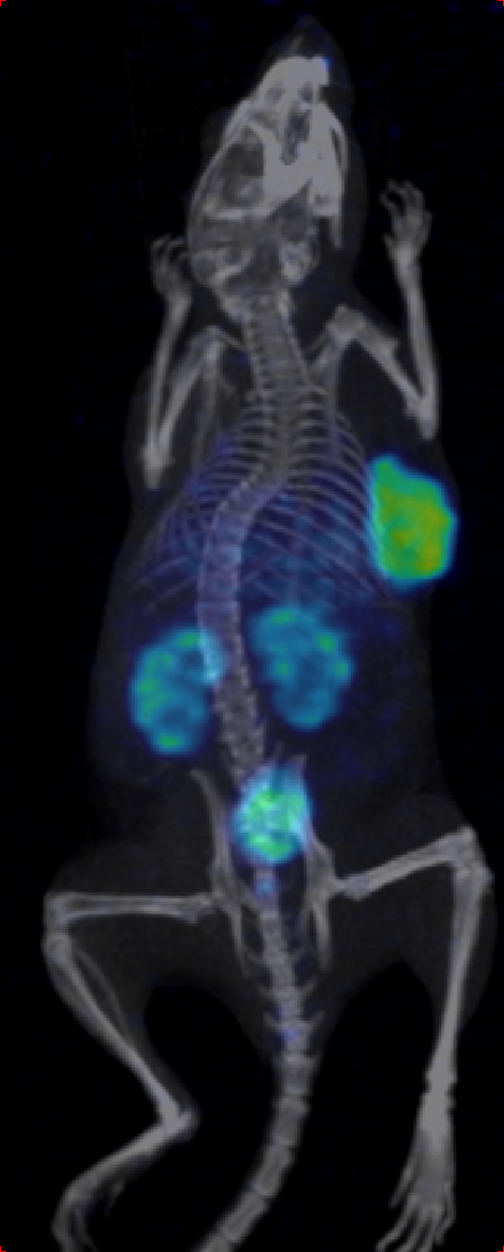

Through quality and process explorations with Zr-89-marked antibody conjugates, highly emissive-pure radiodiagnostic drug molecules are obtained and supplied for preclinical animal imaging and biodistribution studies, as well as subsequent IIT imaging in the clinic.

Rapid validation of Zr-89-marked antibodies

Fast lesion cumulation, most efficient distribution and high targeting ability for xenotransplanted tumor models.